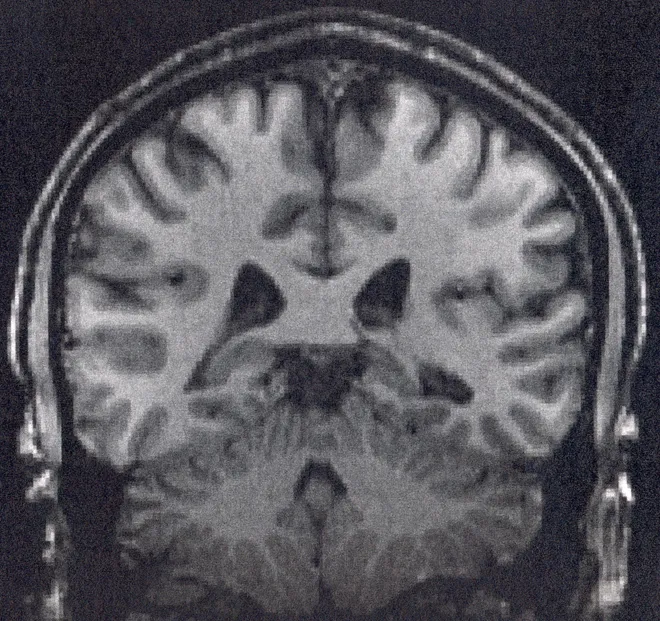

Когда испытуемые просто лежали в томографе, не решая примеров, а просто позволяя мыслям блуждать в полудрёме, прибор показывал странную картину. Отдельные участки коры — медиальная префронтальная область, задняя поясная извилина, латеральные теменные зоны — не затихали, а начинали работать слаженнее и ярче. Они словно вели беззвучный разговор, синхронно пульсируя в такт внутреннему безмолвию.

Рэйчл назвал этот феномен «сетью пассивного режима работы мозга». Для тех, кто изучает природу сознания, эти три буквы — СПРМ — стали обозначением главного рассказчика в нашей голове.

За последующие годы выяснилось, что эта сеть — не просто режим ожидания. Это механизм, который ежесекундно чертит линию между «я» и «всем остальным миром». Именно она создаёт внутренний монолог, тот самый голос, который комментирует, оценивает, тревожится и планирует. Когда СПРМ активна, вы думаете о себе. Когда её активность зашкаливает, вы тонете в липкой паутине тревоги и самокритики, застревая в бесконечных петлях навязчивых мыслей. Повредите эту сеть — и хрупкое здание личности начнёт разрушаться.

В лабораторных условиях было обнаружено, что звук частотой 110 герц способен смещать активность мозга из левого полушария в правое, ослабляя привычный контроль левой височной области. «Рассказчик» начинал замолкать. Граница между телом и пространством таяла, как утренний туман. И тогда происходило необъяснимое: зоны мозга, которые в обычной жизни никогда не обменивались сигналами, вдруг начинали бурную «беседу». Связи возникали хаотично, спонтанно, невероятно гибко. Система не ломалась — она переключалась в режим, который СПРМ обычно держит под замком.

Можно ли считать простым совпадением, что древние шаманские ритуалы с монотонным барабанным боем (около 110 ударов в минуту) и современные акустические эксперименты с частотой 110 герц приводят к одному нейрологическому результату? Подавление активности медиальной префронтальной коры. Ослабление контроля со стороны левого полушария. И, как итог, растворение границы между самостью и окружающим миром.

Исследования, многократно воспроизведённые разными научными группами, показывают устойчивую закономерность: чем сильнее звук определённой частоты меняет баланс активности между полушариями, тем глубже испытуемый описывает чувство единения с миром или выхода за пределы собственного тела. Мозг в этот момент не повреждён. Он просто работает иначе — в режиме, где информация течёт по неожиданным руслам, где рождаются новые связи, где привычный внутренний диалог уступает место тишине.